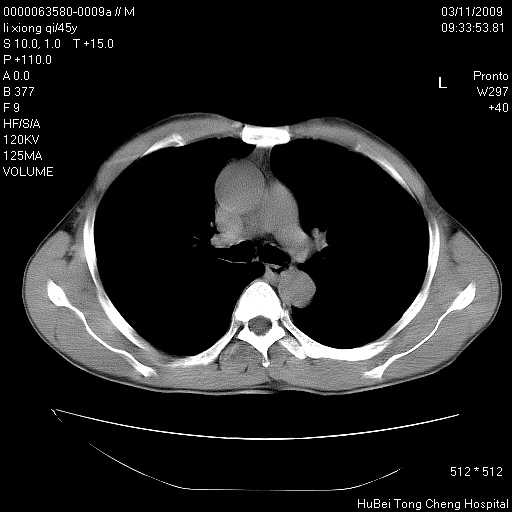

患者 男,45岁。胸痛,咳嗽伴痰中带血1月余。

临床诊断:肺结核?

胸部ct轴位平扫(层厚10mm,螺距1.5,重建间隔10mm),图像如下: